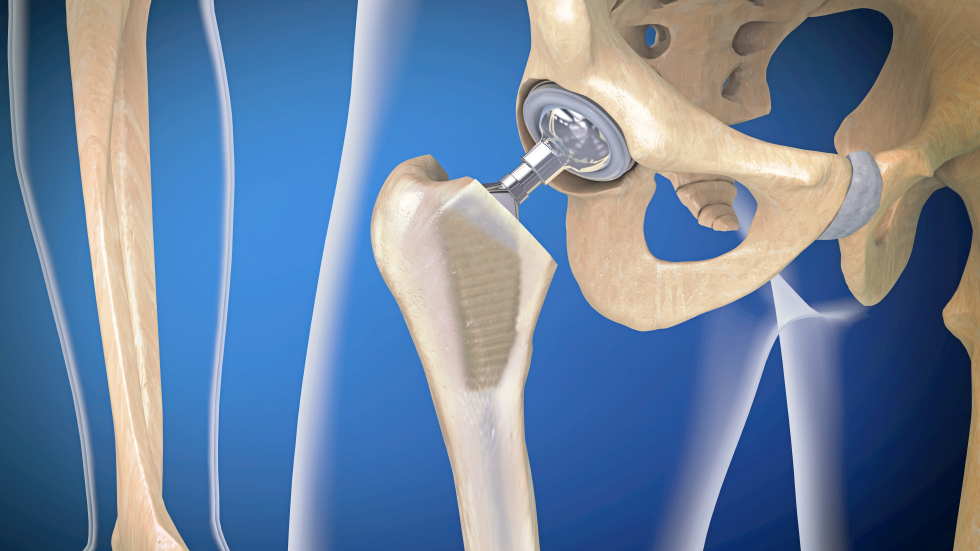

Embora os tratamentos das afecções do quadril datem de séculos atrás, a era moderna da reconstrução do quadril iniciou por volta de 1800. Schmaltz, em 1817, e White, em 1821, relataram casos de ressecção artroplástica do quadril para o tratamento da tuberculose em crianças. Esta técnica operatória também pode ser conhecida como cirurgia de Girdlestone (nome do cirurgião que em 1943 relatou este procedimento com detalhes). Visto que uma mobilidade duradoura não podia ser conseguida desta maneira, muitos autores mudaram da simples artroplastia resseccional para a artroplastia interposicional. O primeiro relato de uso de material estranho colocado entre superfícies articulares, surgiu em 1840, com a colocação de um bloco de madeira posto entre as superfícies. Com o avanço deste tipo de cirurgia, vários tipos de substâncias eram interpostas entre as superfícies resseccionadas, tais como, capsula articular, músculo, tecido adiposo, fáscia lata e pele. Entretanto, nenhum dos materiais usados na interposição produziu resultados duradouros, até que Smith-Petersen desenvolve-se a artroplastia interposicional do quadril com uma taça feita com vitálio, em 1940. A partir de então, muitos cirurgiões começaram a desenvolver endopróteses para reposição de um dos lados da artroplastia como alternativa à artroplastia interposicional. Embora outros materiais tenham sido utilizados na confecção, tais como marfim (Hey-Groves em 1927), acrílico (Judet em 1946), as endopróteses de metal, desenvolvidas por F. R. Thompson e A. T. Moore a partir de 1950, se tornaram os implantes de eleição.

Apesar destes implantes terem proporcionado uma melhora da função, com redução da dor, nenhuma destas hemiartroplastias promoveram um prolongado grau de alívio da dor, buscado por pacientes com articulações artrósicas. Deste modo, desenvolveu-se as substituições articulares totais do quadril. Surpreendentemente, a artroplastia total do quadril não é um produto da metade do século 20. Esta cirurgia foi primeiramente realizada em 1890, por Gluck, que realizou uma artroplastia total de quadril com componentes femoral e acetabular feitos de marfim, cimentados no lugar.

A era moderna da artroplastia por substituição total da articulação teve início em 1958, quando Sir John Charnley começou seu trabalho clássico com o desenvolvimento de uma prótese que consistia de um componente femoral metálico que articulava com um componente acetabular plástico, sendo ambos fixados com cimento ósseo de metilmetacrilato.

O sucesso de uma artroplastia total de quadril depende de 3 fatores críticos: escolha do paciente, escolha do implante e a técnica cirúrgica. Provavelmente, o determinante isolado mais importante seja a escolha apropriada do paciente. A escolha do paciente inadequado pode comprometer o design mais avançado ou mesmo o cirurgião mais experiente. A partir de então, a escolha do implante e a técnica cirúrgica podem nos garantir resultados mais consistentes e duradouros.